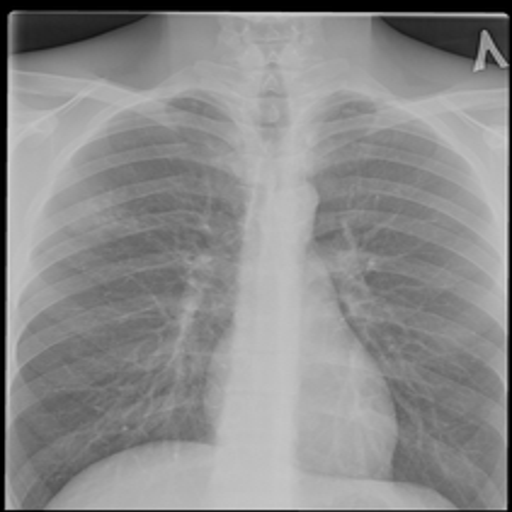

Normal chest X-ray

Healthy TB Prob: 8.6%

Healthy Control

Male, 32y • Routine checkup, asymptomatic

Clear lung fields, normal cardiac silhouette. Verifies model specificity. TB probability: only 8.6%.

BaselineControl